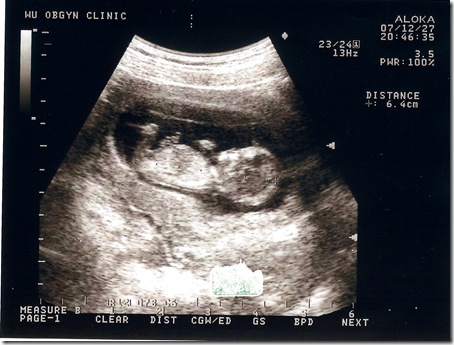

| 地點 | 12/28汐止吳婦產科 | 普通掛號, 超音波 |

| 週數 | 13週 | 這時你如果用手輕輕在腹部碰觸,胎兒就會蠕動起來,但你仍然感覺不到胎兒的動作。 胎兒的神經元迅速地增多,神經突觸形成,胎兒的條件反射能力加強,手指開始能與手掌握緊,腳趾與腳底也可以彎曲,眼瞼仍然緊緊地閉合。 |

| 身長 | 6.4cm | OK |

| 心跳 | 150下/分鐘 | OK |

花了150塊就照了這一張超清楚的照片

醫生也細心地講解各部位的發育

小baby還一邊揮舞著小手 看起來也像是在吸手指..

從右邊的數據可以看到頭臀長己經有6.4公分了

嗯.. 不錯

有乖乖在長大

每次照完超音波我們都很high.. 這次照得超清楚~~ 真好!!